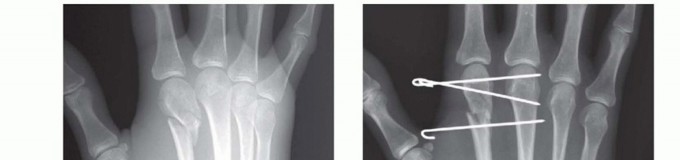

Percutaneous and Intramedullary Techniques

For transverse or short oblique fractures of the metacarpal neck and shaft, particularly in the fifth metacarpal, percutaneous or minimally invasive intramedullary techniques offer excellent stability while sparing the dorsal soft-tissue envelope. The procedure begins with a closed reduction utilizing the Jahss maneuver: the MCP and PIP joints are flexed to 90 degrees, relaxing the intrinsic muscles and tightening the collateral ligaments, allowing the proximal phalanx to be used as a lever to push the metacarpal head dorsally, correcting the apex-dorsal angulation.

Once reduced, fixation can be achieved via crossed Kirschner wires or retrograde intramedullary pinning (the "bouquet" technique). However, the modern gold standard for minimally invasive fixation is the retrograde intramedullary headless compression screw. A small stab incision is made over the dorsal aspect of the flexed MCP joint. The entry portal is meticulously established in the articular "safe zone" of the metacarpal head—specifically the dorsal-ulnar or dorsal-radial collateral recess, strictly avoiding the central weight-bearing articular cartilage.

A guidewire is advanced down the medullary canal across the fracture site under fluoroscopic guidance. After confirming perfect rotational alignment and length, the canal is sequentially broached or drilled, and an appropriately sized headless compression screw is buried beneath the articular cartilage. This technique provides robust, load-sharing stability that allows for immediate, unrestricted active range of motion, vastly reducing the incidence of postoperative stiffness compared to traditional K-wire constructs.

Clinical & Radiographic Imaging Archive